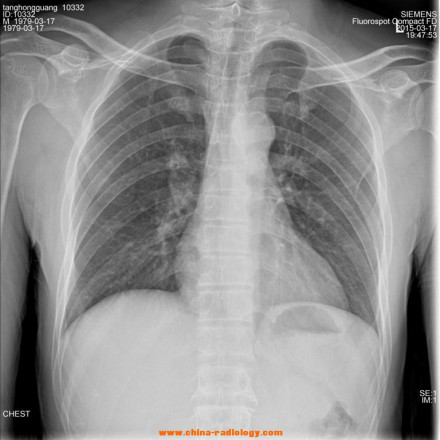

X射线应用于医学诊断,主要依据X射线的穿透作用、差别吸收、感光作用和荧光作用。由于X射线穿过人体时,受到不同程度的吸收,如骨骼吸收的X射线量比肌肉吸收的量要多,那么通过人体后的X射线量就不一样,这样便携带了人体各部密度分布的信息,在荧光屏上或摄影胶片上引起的荧光作用或感光作用的强弱就有较大差别,因而在荧光屏上或摄影胶片上(经过显影、定影)将显示出不同密度的阴影。根据阴影浓淡的对比,结合临床表现、化验结果和病理诊断,即可判断人体某一部分是否正常 。

1、感光作用。X射线同可见光一样能使胶片感光。胶片感光的强弱与X射线量成正比,当X射线通过人体时,因人体各组织的密度不同,对X射线量的吸收不同,胶片上所获得的感光度不同,从而获得X射线的影像 。

X射线诊断